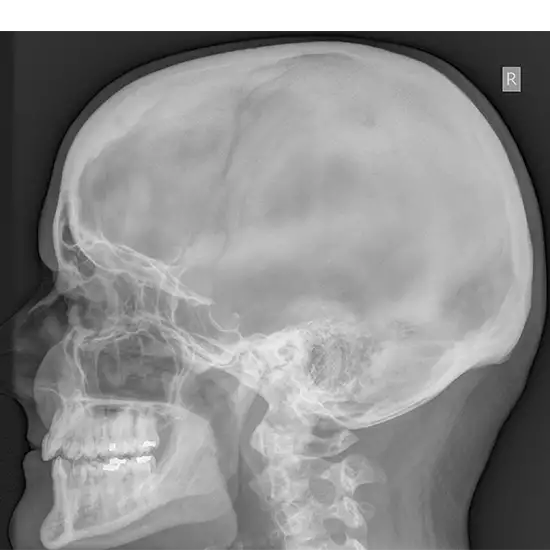

X-Ray both mastoids, which is a bone of the skull and may be found directly behind the ear, can be visualized with the help of the LAT and Obl tests. This bone is made up of air-filled gaps and cells, both of which contribute to the drainage and cleanliness of the ear.

The physician will recommend that you undergo this examination to determine whether or not you are suffering from an infection of the air spaces within the mastoid bone or whether or not you have a tumor in the region surrounding the mastoid bone.